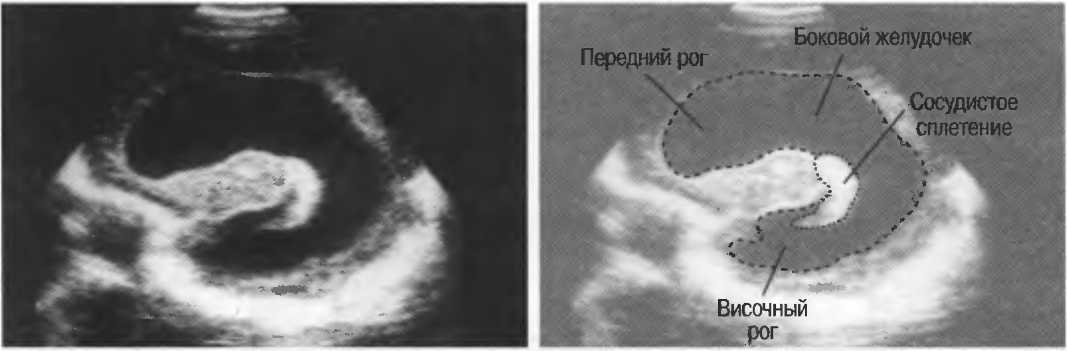

Прозрачная перегородка узи

Прозрачная перегородка узи 109 фотографий